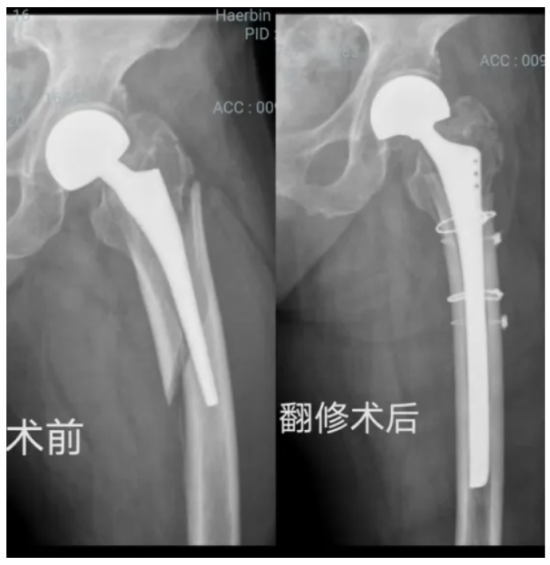

经过充分的术前准备后,手术正式开始。骨外一科返聘专家李德怀、副主任孙志海带领的专家团队紧密配合,为患者精准拆除了原假体,清除界面纤维组织,植入加长翻修柄,并用钛缆进行加固,重建了髋关节的稳定性。历时2.5小时,手术顺利完成。术中出血量控制在400ml以内,患者生命体征始终保持平稳。